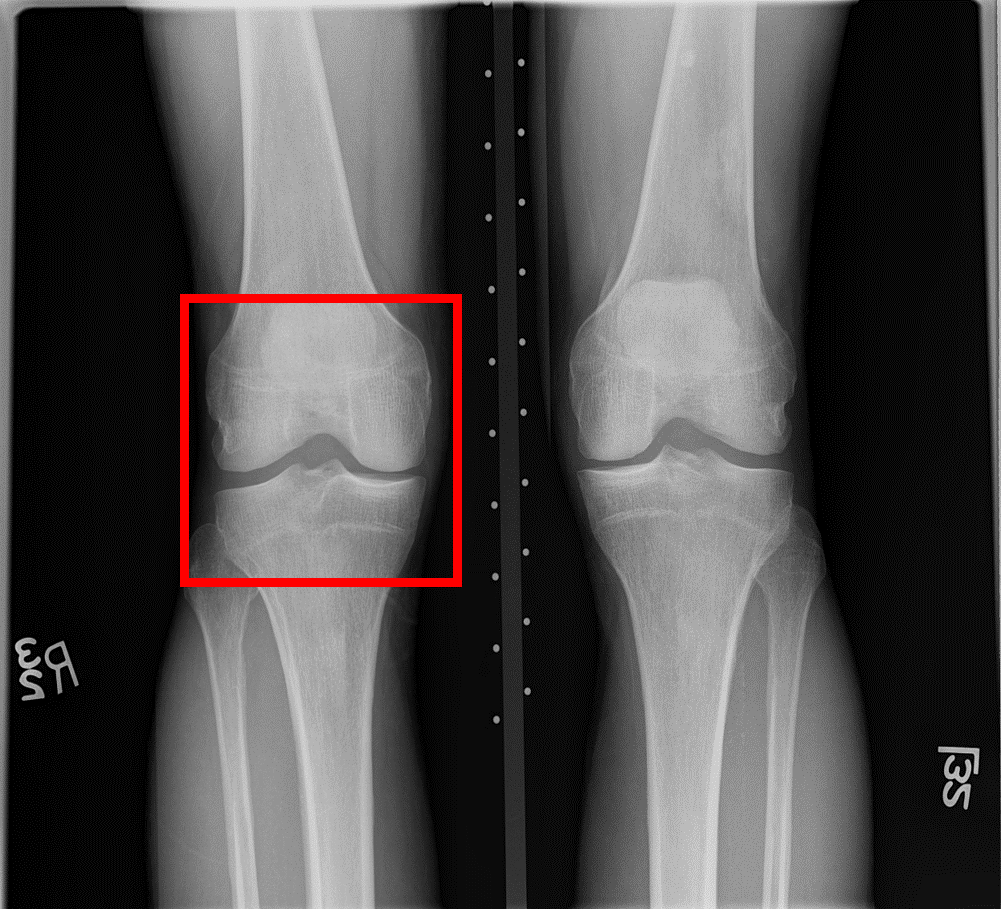

Since the aim of this study is the early detection of knee OA (KL=0 vs. KL=2), we focused on the characteristics of the lateral and medial sides of the knee joint. We used the same ROIs as [chen] available at put a reference for the link. ROIs were extracted from the original X-ray images using YOLOv2 [yolov2]. Then, the fully automatic segmentation method proposed in [tiuplin] to extract the patches was used. Firstly, two 128×\times×128 pixel square patches were cropped from the left and right parts of the knee joint to cover the whole distal area. Secondly, the patch from the medial side was flipped horizontally. Finally, the two patches were used as inputs of the learning model.

Refer to caption

Figure 3: (a) Original knee radiographs from OAI, extracted ROI in red. (b) Obtained patches in blue and orange boxes. (c) Extracted patches for the two sub-networks respectively